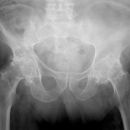

Fraktur Ramus pubis sup. und inf.